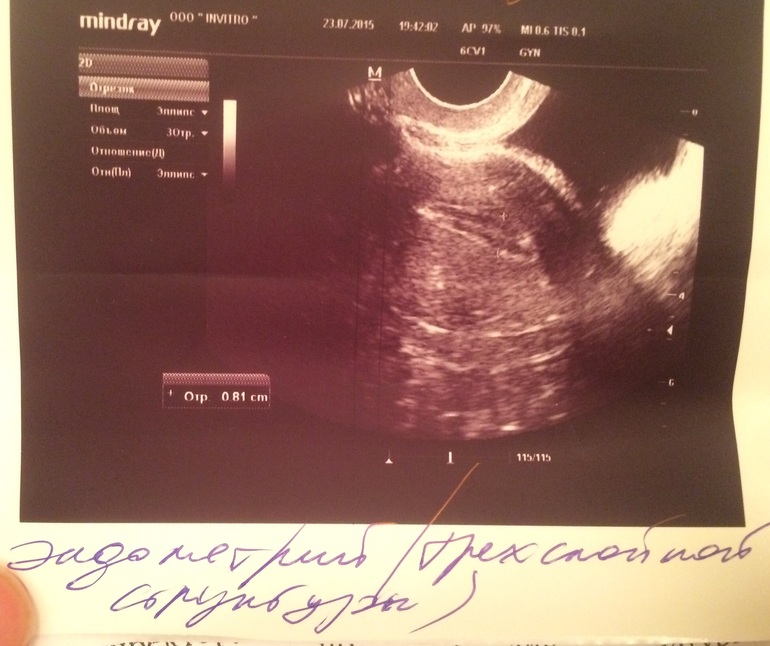

Шол 11 дц.... Неделю назад была на узи (4 дц) сказали эндик 3 мм-мало, ДФ слева 10 мм..... Я как то растроилась и пошла домой думать как же нарости ть его.... На 8 дц побежал ЯБ в огромных количествах.... Стала делать тесты

Ммм, девочка моя! Трехслойный! 23 мм на 11 ДЦ! Шикаарно! У меня так же было в беременный цикл (если помнишь))) Тестик прям поярчал. Жди дня через 2 О. С Богом!!!! Апчхи на тебя! Заразным беременным!!!! Апчхи! У нас первые толчки как раз))) Апчхи!!!!